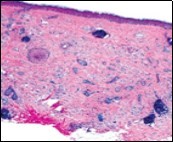

Lesions are generally superficial and infrequently invade lower dermis. Tendency for peri-neural or intra-neural infiltration, cogitated in adjunctive cutaneous carcinomas, is exceptional in desmoplastic trichoepithelioma. Nevertheless, desmoplastic trichoepithelioma can be exemplified as a component of particularly desmoplastic, cutaneous carcinomas demonstrating foci of peri-neural involvement 4, 5. Figure 1, Figure 2, Figure 3, Figure 4, Figure 5, Figure 6, Figure 7, Figure 8.

Figure 3.Desmoplastic trichoepithelioma exhibiting accumulated basaloid epithelial cells disseminated amongst a background of abundant fibrous tissue stroma and an attenuated superimposed epidermis 10.